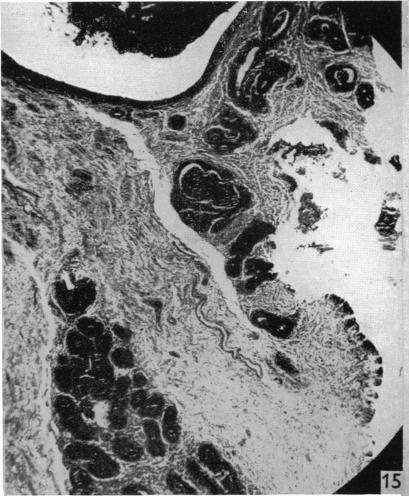

The male reproductive tract of the fowl.

J Anat. 1957 Jan;91(1):116-29.